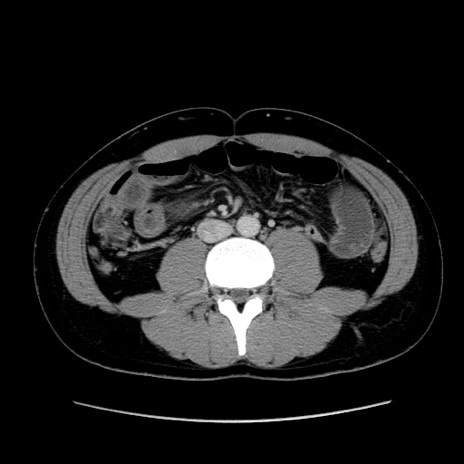

症例36(横断像)

【症例】20歳代 男性

【主訴】心窩部痛

【現病歴】今朝より上腹部痛あり。一旦軽快していたが再度出現したため救急要請。昨日夕に白身の魚を含む刺身を食べた。

【身体所見】BP 136/89mmHg、HR 74/min、BT 37.0℃、腹部:膨満、軟、心窩部に圧痛あり。反跳痛なし、筋性防御なし、腸雑音やや亢進あり。

【データ】WBC 17700、CRP 0.48